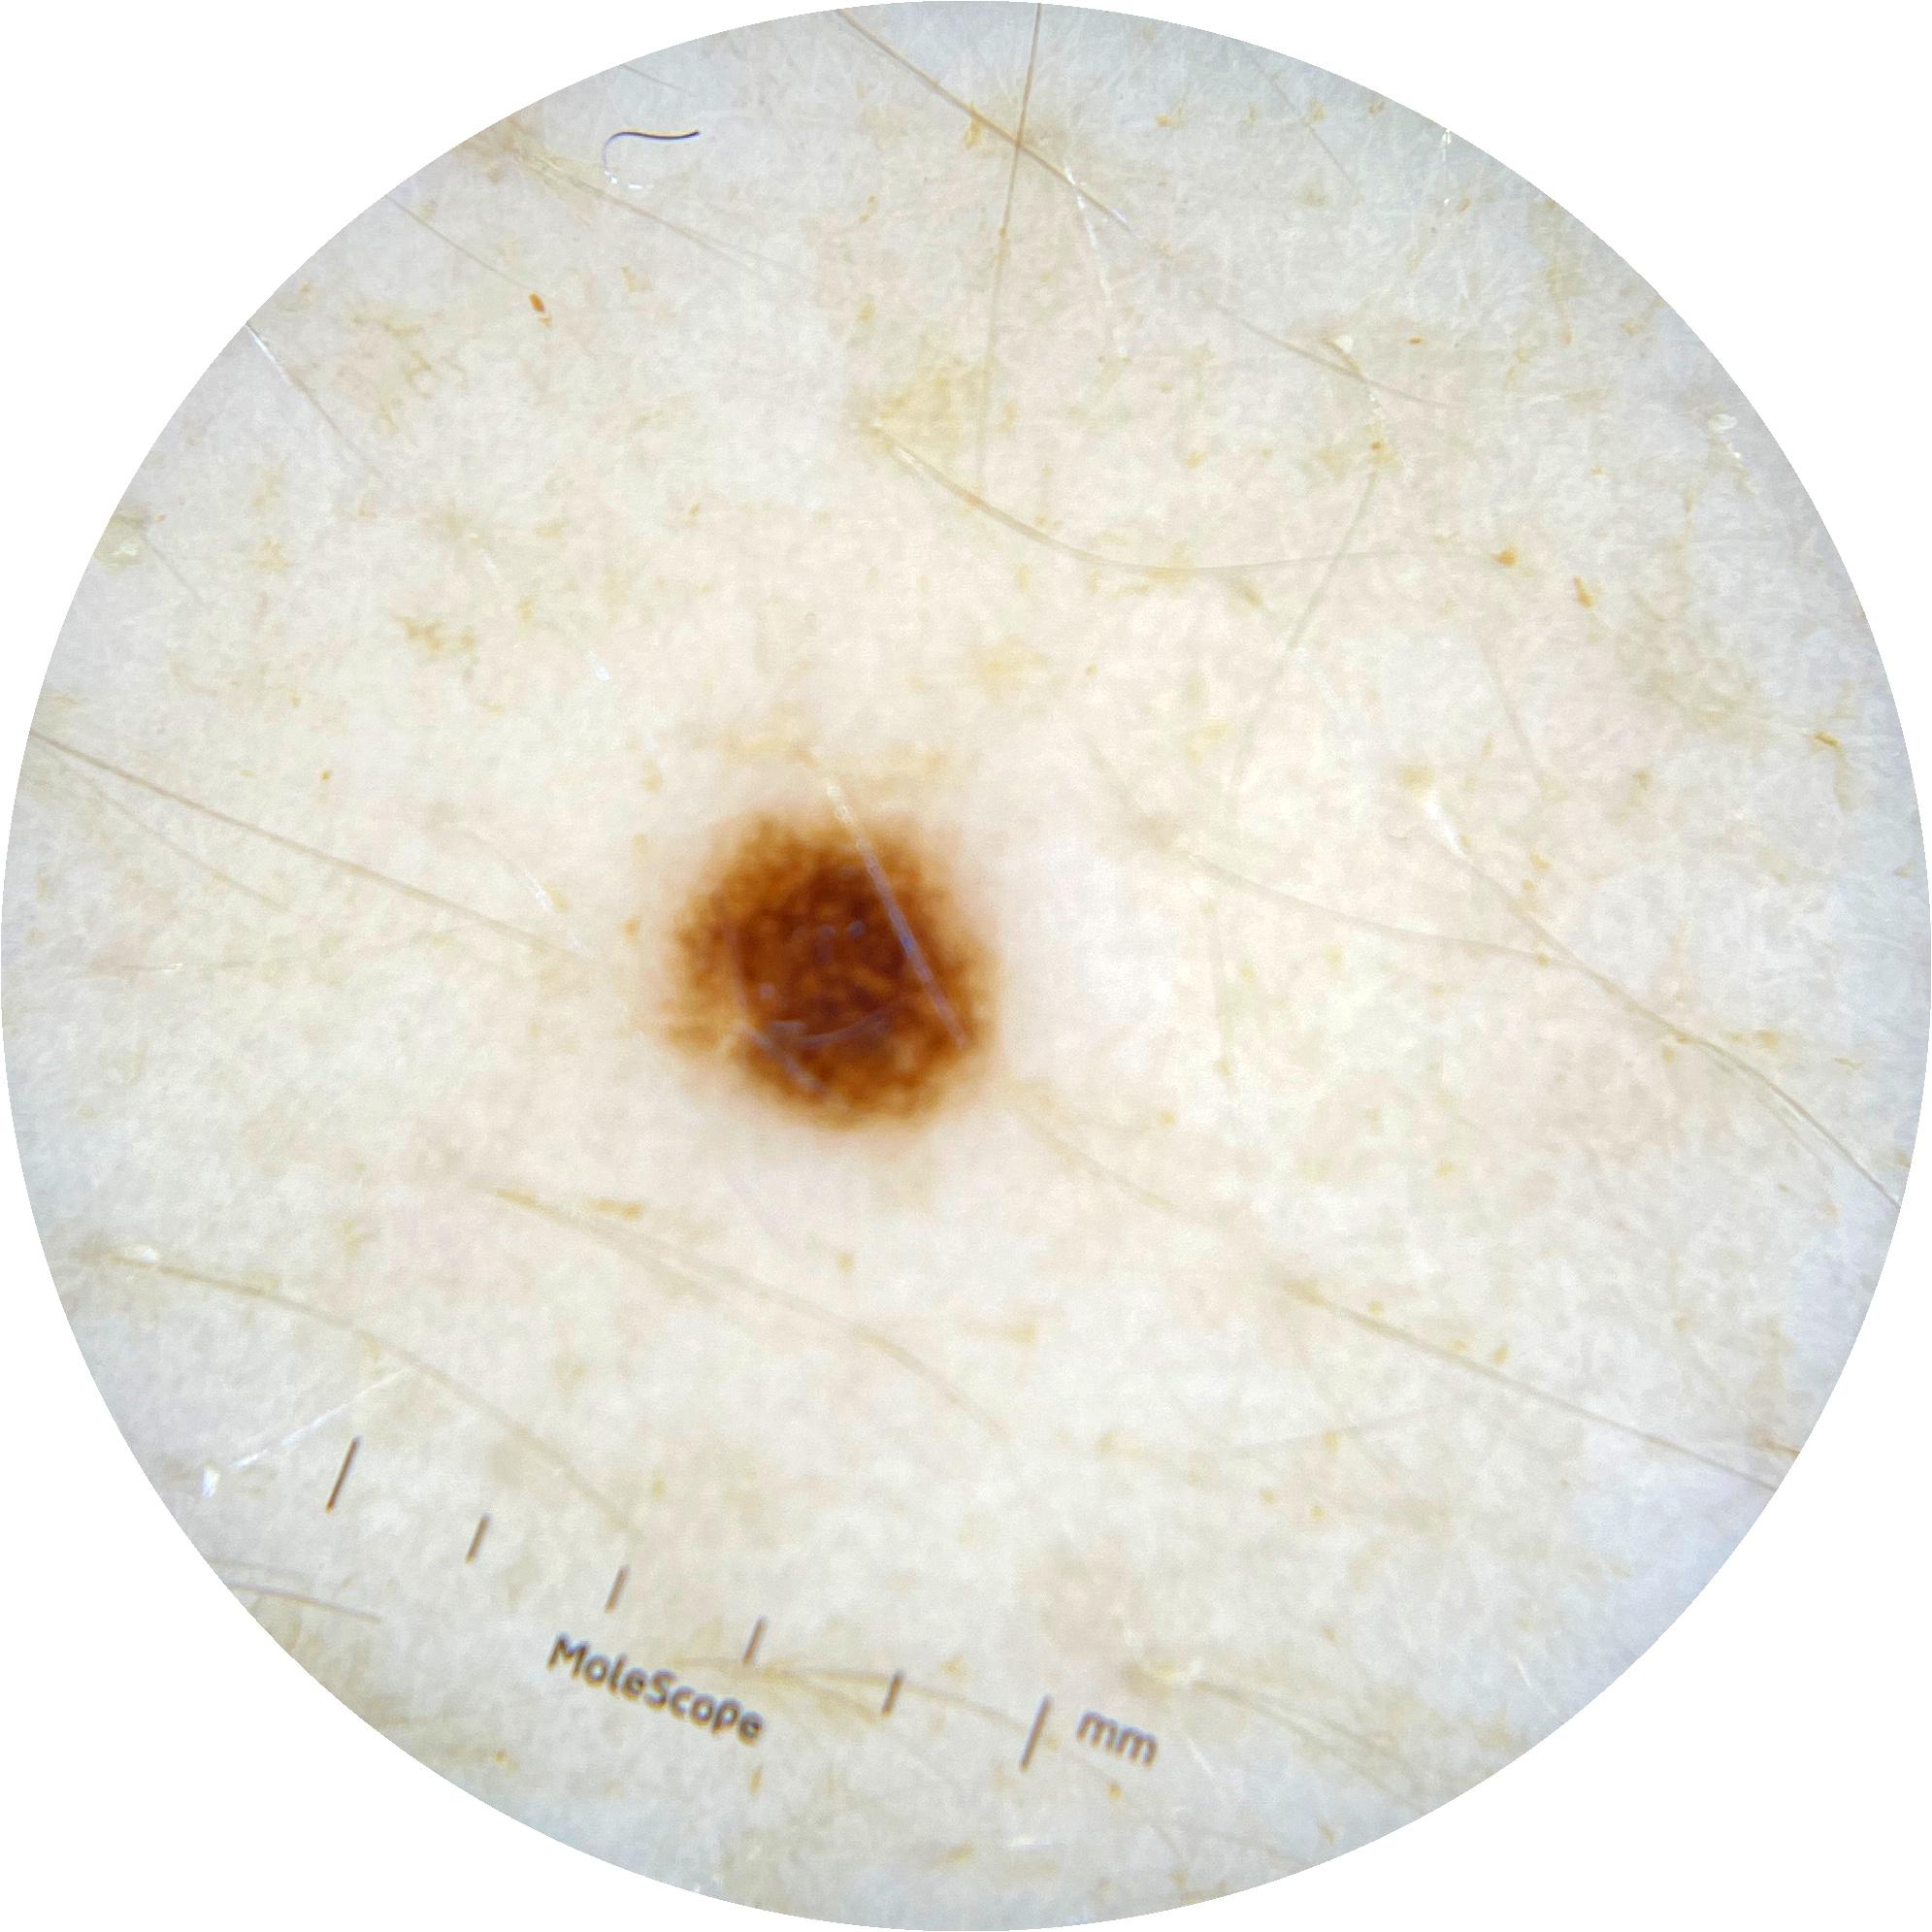

ISIC_0301375

1986 x 1986

Clinical

Field Value

acquisition_day 331

age_approx 35

anatom_site_1 Trunk

anatom_site_2 Anterior trunk

anatom_site_general anterior torso

concomitant_biopsy False

diagnosis_1 Benign

diagnosis_confirm_type single image expert consensus

family_hx_mm False

fitzpatrick_skin_type II

image_manipulation instrument only

image_type dermoscopic

lesion_id IL_8028733

patient_id IP_7964478

personal_hx_mm True

sex female